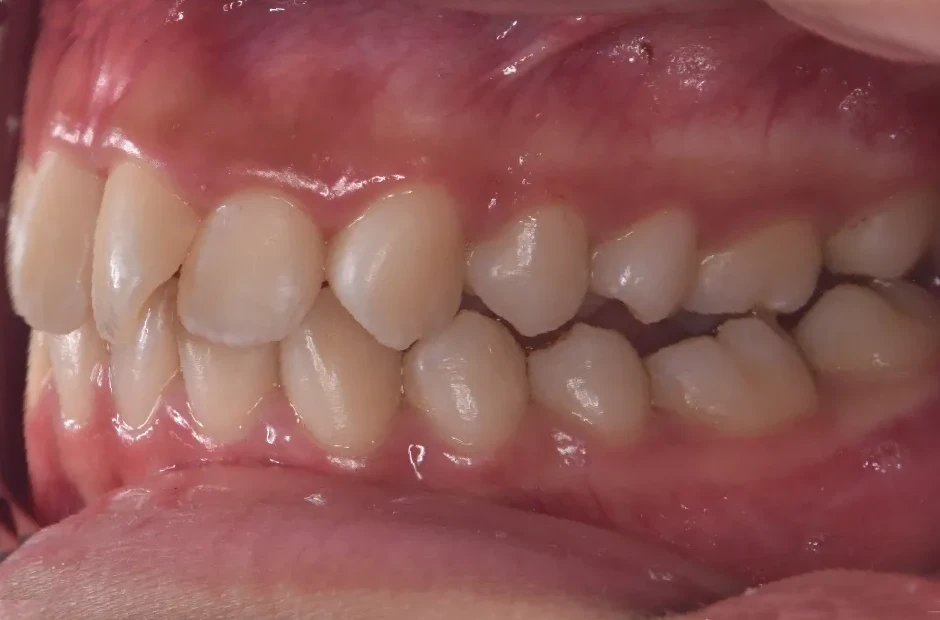

治療症例

ブラケット矯正

前歯部反対咬合

| 診断名・主訴 | 前歯部反対咬合 |

|---|---|

| 年齢・性別 | 14歳・男性 |

| 治療期間・回数 | 1年2か月 |

| 治療に用いた主な装置 | ブラケット矯正 |

| 抜歯部位 | なし |

| 治療費 | 60万円(税抜) |

| リスク・副作用 | 装置による違和感・疼痛・歯肉退縮・歯根吸収・虫歯のリスクなど |

治療前

治療中